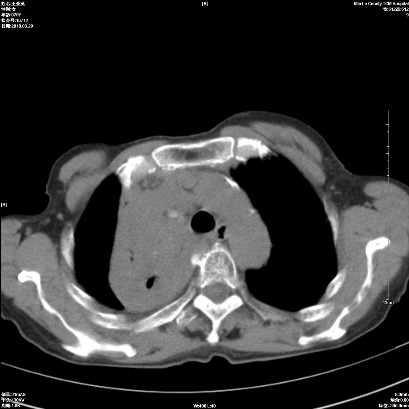

右肺上叶支气管开口阻塞,上叶呈不均匀致密影,右肺中下叶内见斑片状密度增高影,上叶见钙化点,纵隔内见钙化淋巴结,桶状胸,右下肺动脉增粗,残根征,意见:1.右肺中心性肺癌;2.右肺陈旧性结核;3.肺心病。

ct所见:右肺上叶肺不张,呈软组织密度影向肺门区聚拢,其内可见含气段支气管及细支气管影,病灶内尚可见钙化结节。右肺上叶支气管狭窄,段支气管壁可见钙化。右肺下叶背段、右肺中叶见不规则小片絮状影及纤维条索影,形态较僵硬。右肺中叶胸膜旁可见多个小结节影。纵膈内见钙化淋巴结。

分析:右侧胸廓及右肺体积缩小,说明病变时间比较长了,应该是有数年的时间了,如果是短期内出现的肺不张,只会引起纵膈向患侧移位,而不会引起胸廓的塌陷。不张的肺组织内可见含气支气管影,说明右肺上叶支气管没有完全中断,只是狭窄。右肺中叶、下叶散在不规则病灶,部分呈纤维化改变。纵膈内的淋巴结大部分钙化。因此,本例给我的感觉良性病变的可能是大。

结论:考虑右肺上叶支气管内膜结核合并右肺上叶肺不张;右肺中叶、下叶陈旧性肺结核改变。